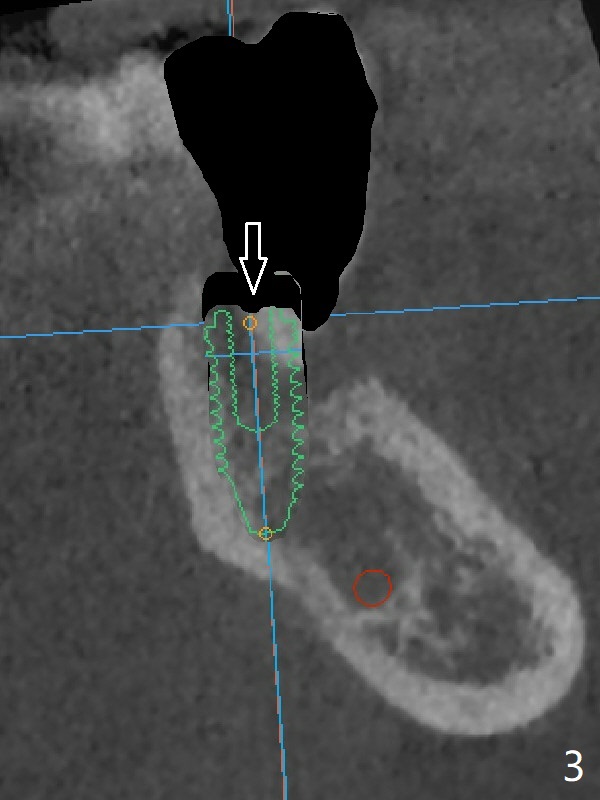

A 67-year-old man requests treatment for the tooth #19 with severe buccal gingival recession (Fig.1). After extraction, a 5x11.5 mm implant will be placed as lingual as possible (Fig.2 L) with ~7 mm buccal implant thread exposure. To reduce the exposure, the implant will be placed deeper, as shown by arrow in Fig.3. PRF membrane and collagen membrane (Fig.4 red line) will be placed against the buccal gingiva, while PRF associated sticky bone (allograft, pink circle) will be packed around the exposed implant threads and a long-cuff abutment (yellow). Finally an immediate provisional (Fig.5 white) will be fabricated to cover the bone graft.